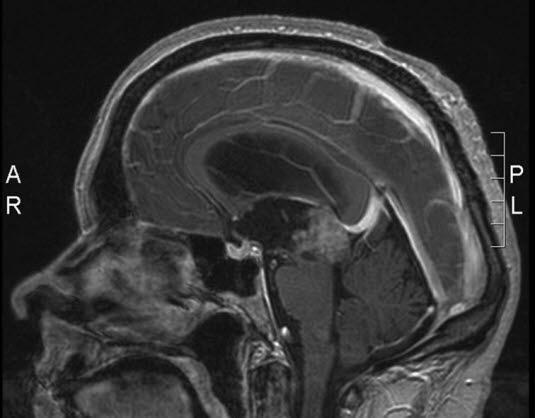

Pineocytom, sagittalt snitt

Gjengitt med tillatelse av Radiologisk avdeling, Universitetssykehuset Nord-Norge